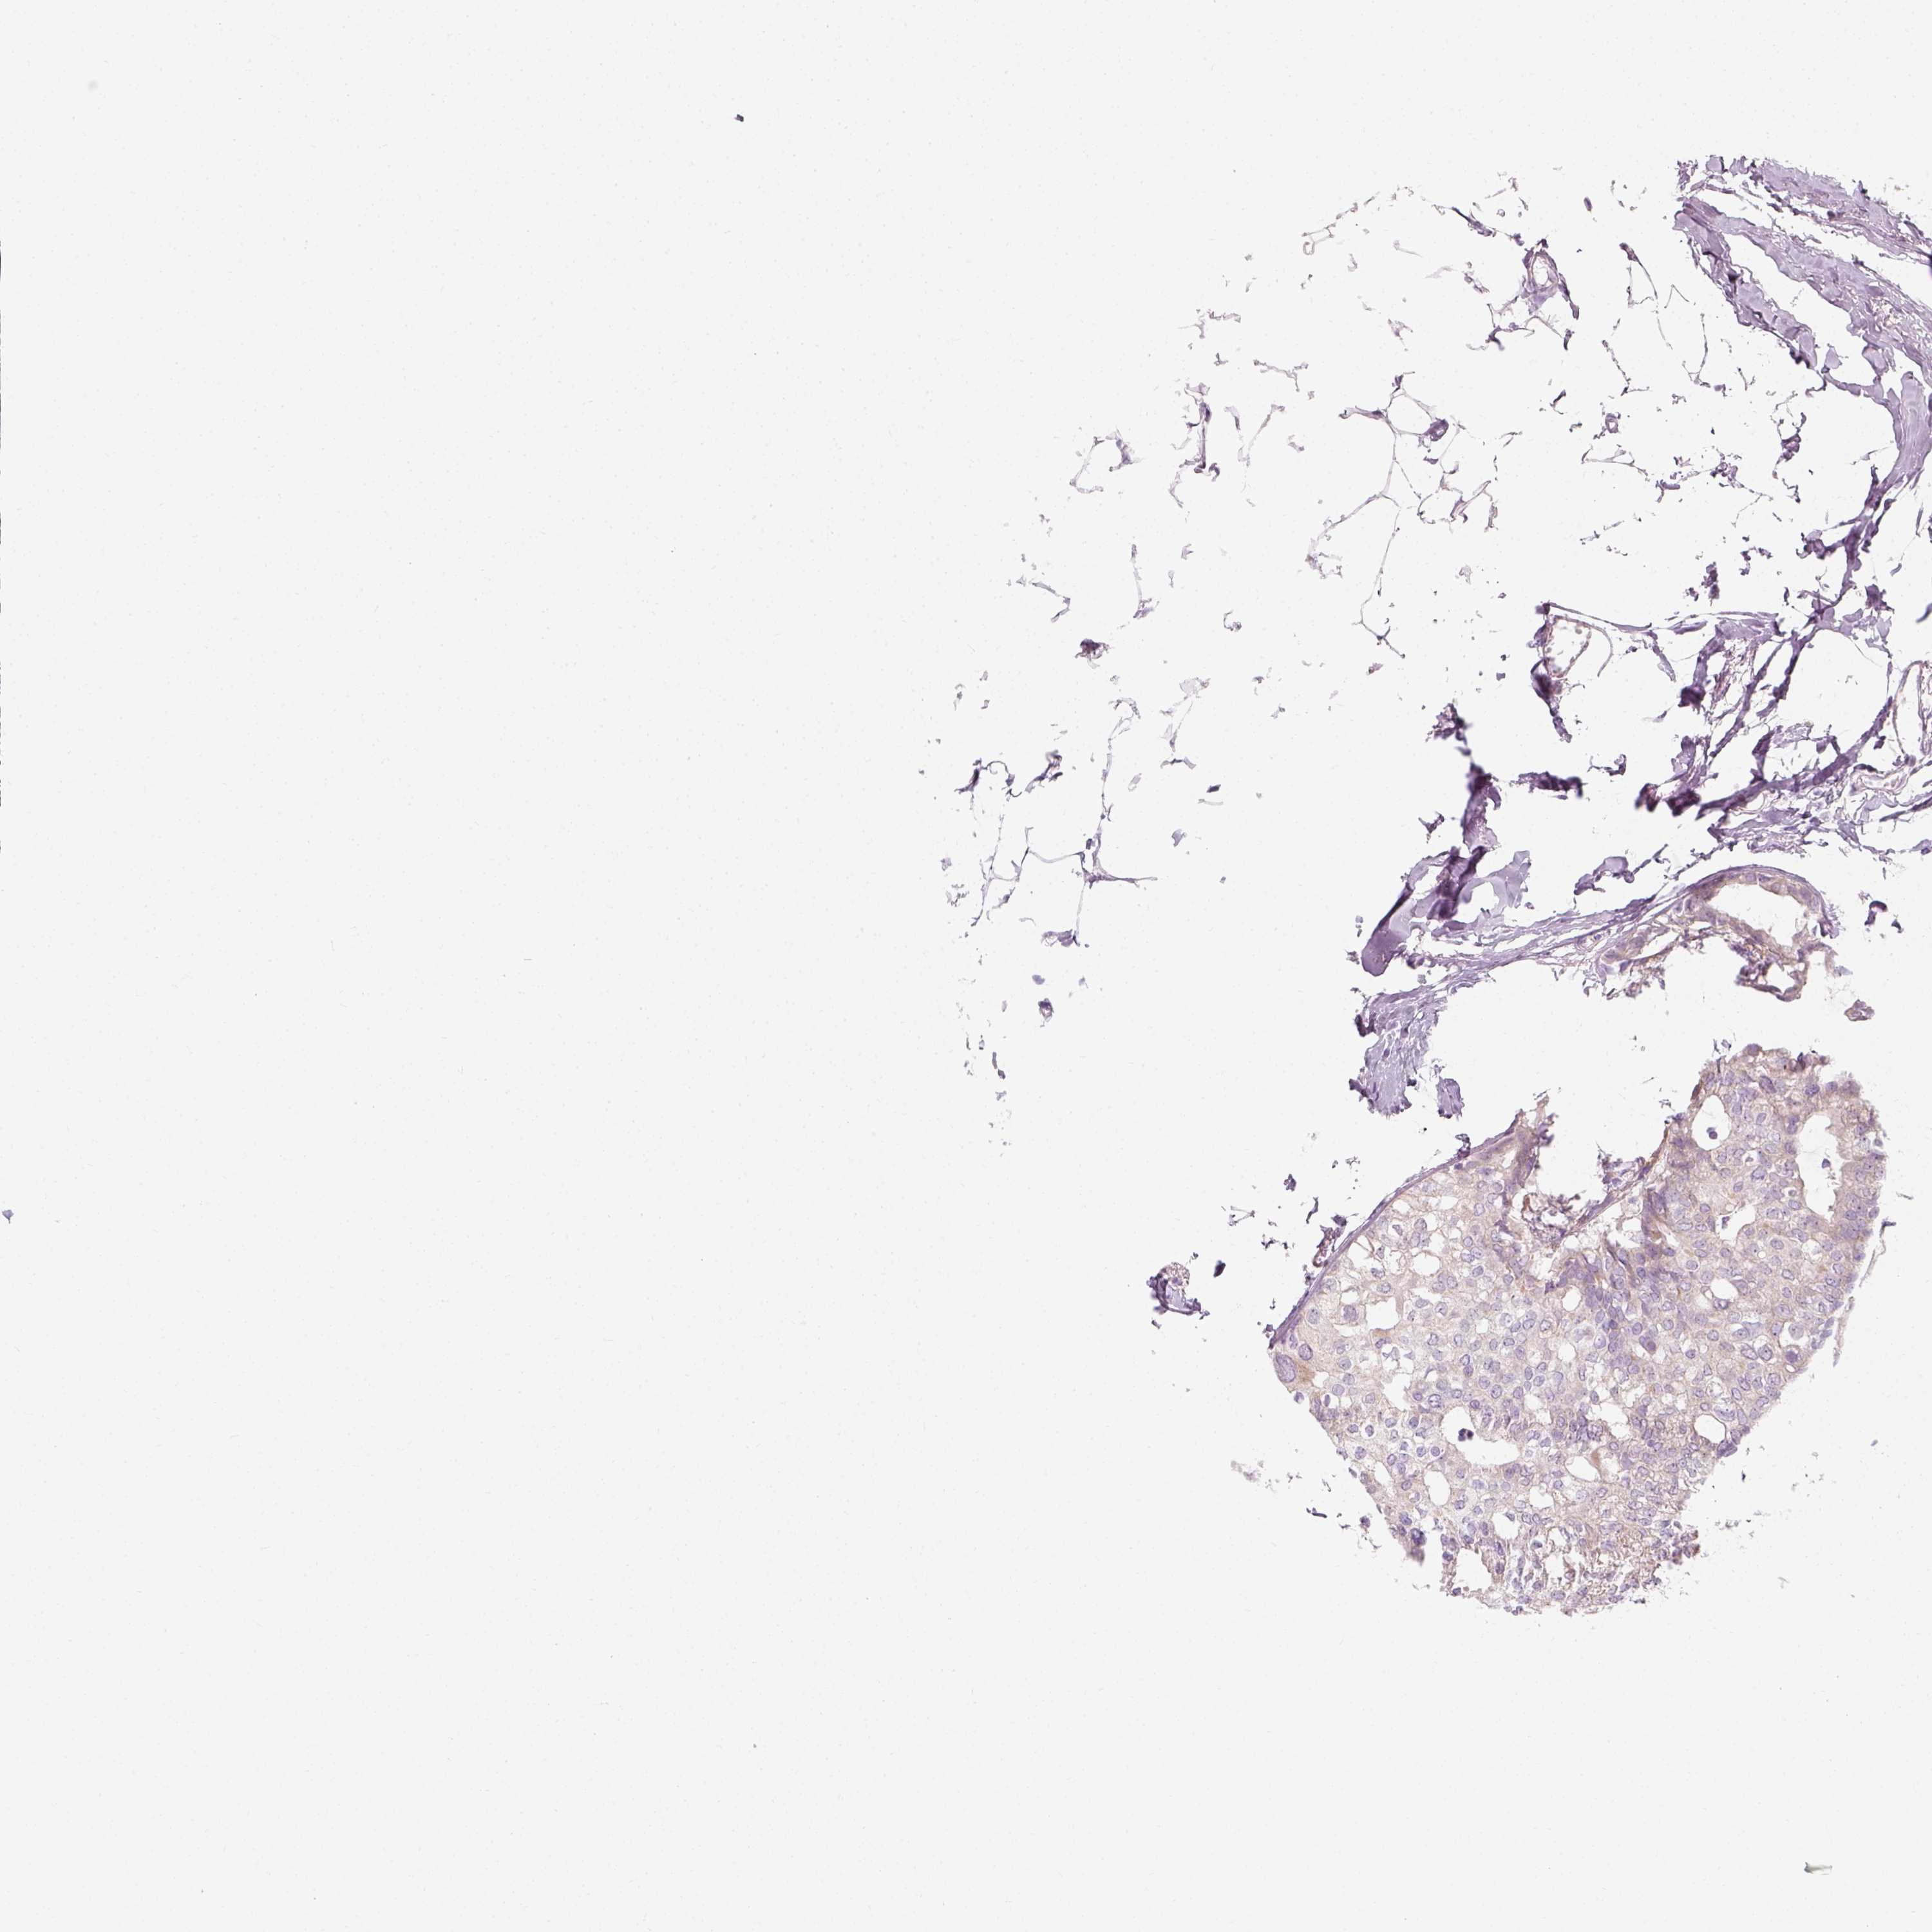

CANCER BREAST CANCER Show tissue menu

BRCA TCGA BRCA VALIDATION PROTEIN EXPRESSION